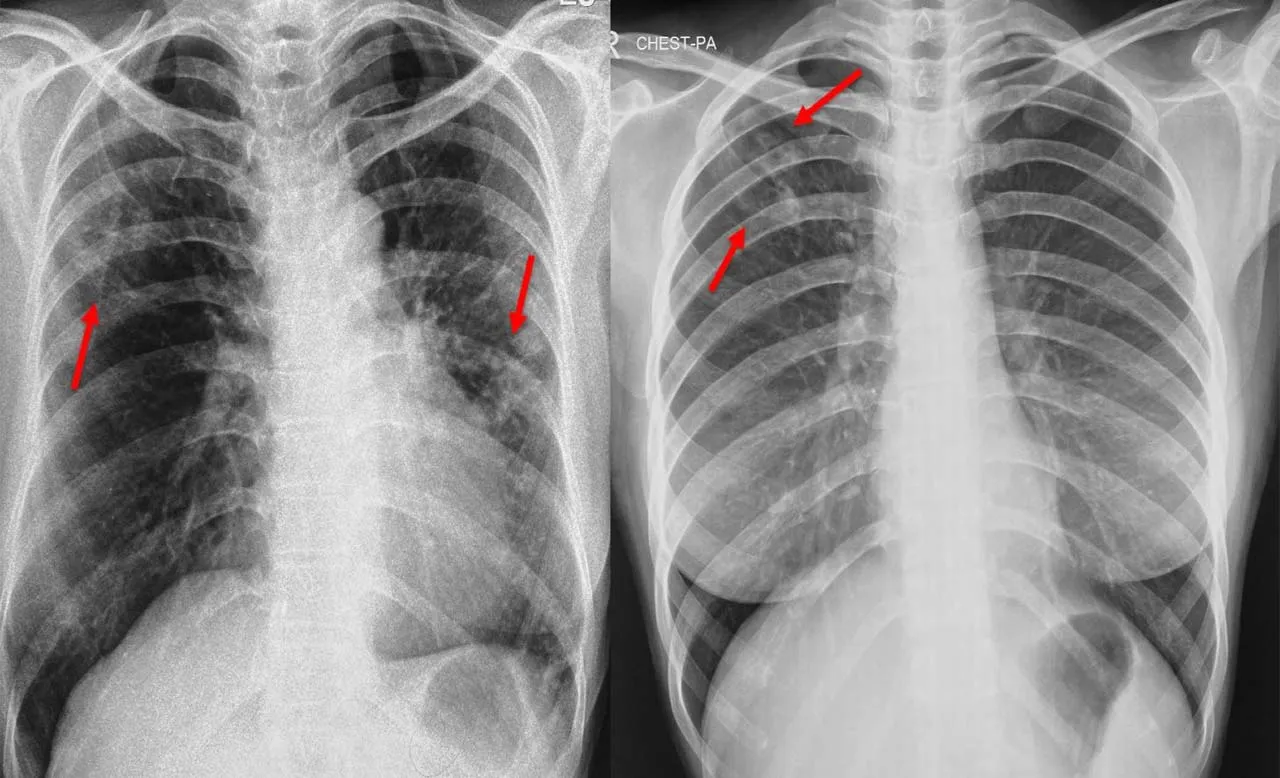

लखनऊ, अमृत विचार। हर चमकती चीज जैसे सोना नहीं होती, उसी तरह से फेफड़ों के एक्स-रे में दिखने वाला हर धब्बा टीबी नहीं होता। टीबी की सटीक पहचान के लिए एक्स-रे की बारीकियों की जानकारी होना जरूरी है।

कार्यशाला में नौ राज्यों के करीब 250 पीजी छात्र शामिल हुए। डॉ. सूर्यकांत ने बताया फेफड़ों के एक्स-रे से केवल टीबी ही नहीं बल्कि कई अन्य बीमारियों के बारे में भी सावधानीपूर्वक पता लगाया जा सकता है। इनमें तो कई ऐसी बीमारियां भी होती हैं जो एक्स-रे में टीबी जैसी ही लगती हैं।

उन्होंने बताया कि इन बीमारियों में प्रमुख रूप से लंग कैंसर, इंटरशियल लंग डिजीज (आईएलडी), सीओपीडी, एक्यूट रेस्परेटरी डिस्ट्रेस सिंड्रोम (एआरडीएस), निमोनिया, ट्रोपिकल पल्मोनरी ईओसिनोफीलिया (टीपीई), लंग फाइब्रोसिस, ब्रान्काइटिस शामिल हैं।